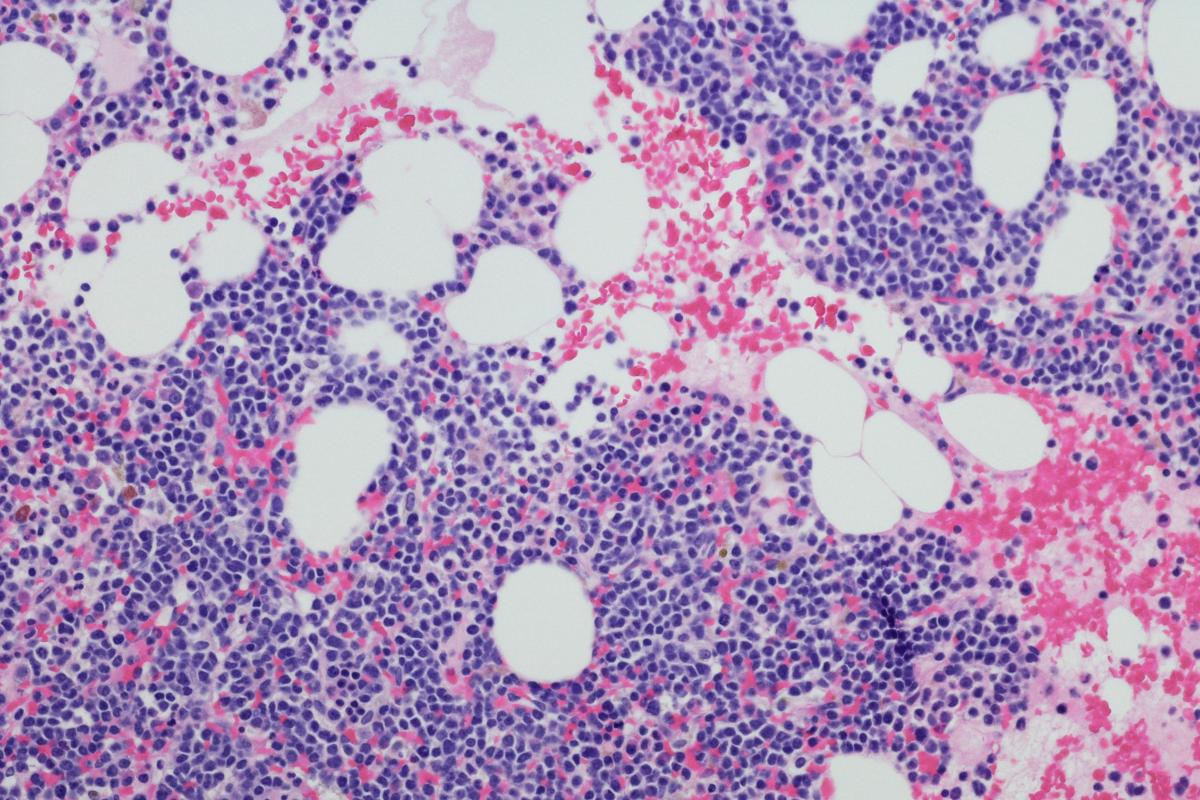

Se trata del Blenrep, un fármaco indicado para tratar el mieloma múltiple.

La FDA, la agencia del medicamento de Estados Unidos, ha ordenado retirar el Blenrep, un tratamiento innovador contra el cáncer de la farmacéutica británica GSK tras fallos en un ensayo clínico, tal y como informa El País.